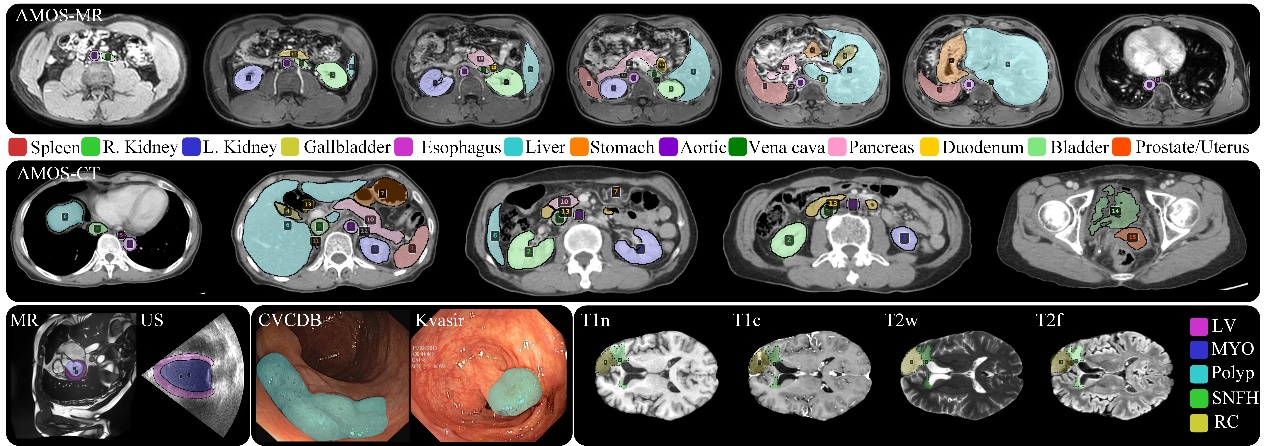

图2 可视化结果